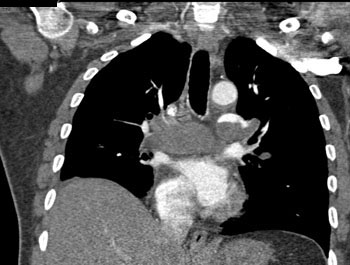

|  | Question 13: A 55 year old man with past medical history of pulmonary hypertension, systemic hypertension, and hyperlipidemia presented with dyspnea. A contrast enhanced computed tomography (CT) scan revealed bilateral pulmonary emboli. Patient was started on anticoagulation and discharged home uneventfully. A repeat CT weeks later suggests? |